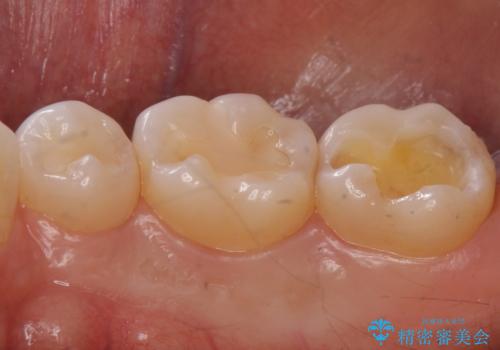

欠けた部分にはセラミックインレーで修復処置を行い、今後の破折リスクを抑えるためにナイトガードを製作していきます。

食いしばりが強い方はセラミックがまた割れる可能性があるため、予防的にナイトガードを装着することをお勧めします。